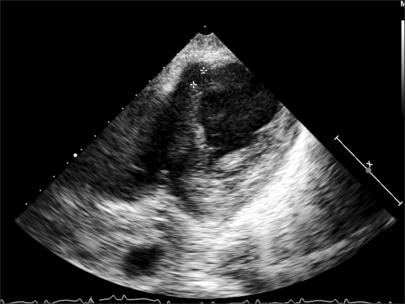

We report a case of a postinfarction ventricular septal defect caused by an acute recurrent occlusion after the implantation of a covered stent, which was performed as a rescue procedure for the ruptured left anterior descending artery during a percutaneous coronary intervention. Although the emergent implantation of a covered stent for the ruptured coronary arteries such as the left main coronary artery or the origins of the left anterior descending artery can be performed during a percutaneous coronary intervention, and a coronary bypass surgery should be considered in order to decrease the risk of complete occlusion, thus providing a superior long term patency.

我们报告了一例在植入覆膜支架后因急性复发性闭塞导致的心肌梗死后室间隔缺损病例,该覆膜支架植入是在经皮冠状动脉介入治疗期间作为左前降支破裂的抢救措施进行的。尽管在经皮冠状动脉介入治疗期间可以对诸如左主干冠状动脉或左前降支起始部等破裂的冠状动脉进行覆膜支架的紧急植入,并且应考虑进行冠状动脉搭桥手术以降低完全闭塞的风险,从而提供更好的长期通畅率。